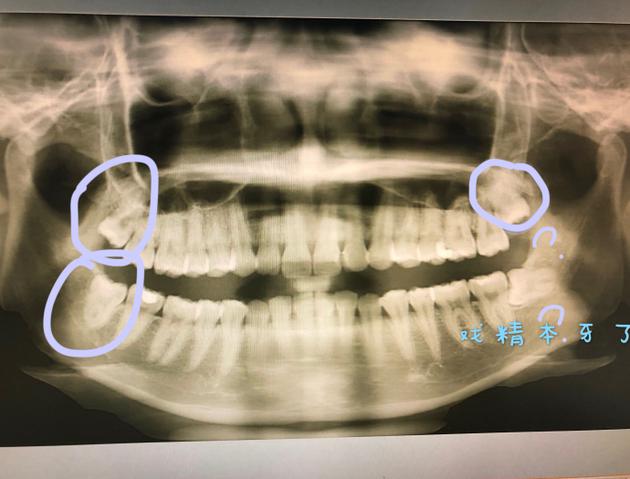

吴宣仪晒照自曝将拔智齿 调侃自己的牙是戏精